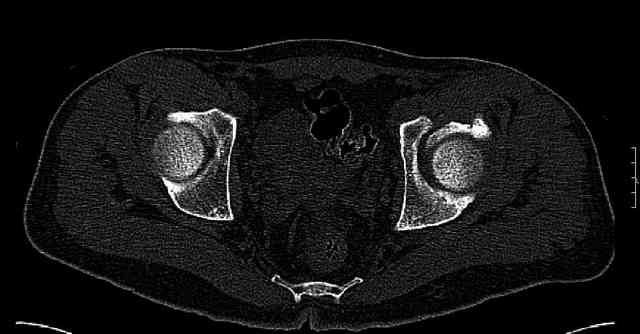

Some more images. Does it help to guess which part of the acetabulum is displaced?

Normal appearing SI joints and a healed posterior column limb... my bet's on caudal segment displacement.